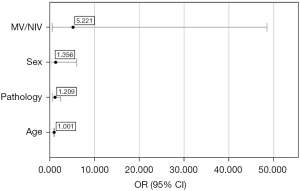

Logistic regression did not yield statistically significant results for any of the variables when analysed together with age, sex, ventilation mode, and the size of lung pathology (Figure 3). The model included age, sex, MV/NIV ventilatory strategy, and chronic pre-existing lung pathology. The model produced was calculated by SPSS to reflect reality (P<0.001), and the predictive value of the model was 78.3%. The lowest odds ratio was obtained for the age variable however, the result is statistically not significant [odds ratio (OR) =1.001, 95% confidence interval (95% CI): 0.937–1.068, P=0.985]. The odds ratio for lung pathology was 1.209, but the results are also not significant (95% CI: 0.597–2.450, P=0.598). The odds ratio for sex was 1.356 with a confidence interval of 0.304–6.047, which is statistically not significant (P=0.689). For ventilation, we obtained the highest odds ratio of 5.221 with a confidence interval of 0.562–48.515 and the lowest significance value but it was also statistically not significant (P=0.146) (Figure 3).